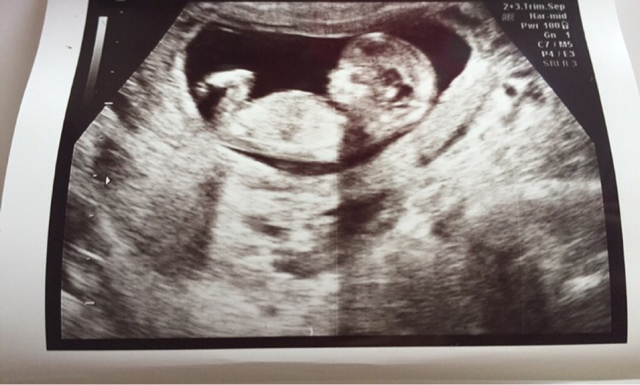

Tässä vertailuksi haamu kun olin raskaana :) ja edelleen olen.

Haiidi, onnea hyvistä ultra kuulumisista.

Haiidi, onnea ultrakuulumisista

Haiidi onnea ihanista ultrakuulumisista :)

Haiidi, onnea! Ihana ultrakuva :Heartpink